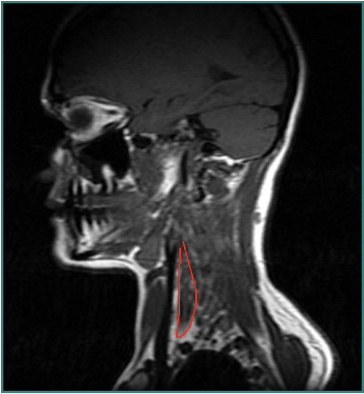

Larynx shifted relative to sternum

Lateral Shift

Secondary to lateral flexion of the spine and flexion of the head in the opposite direction.